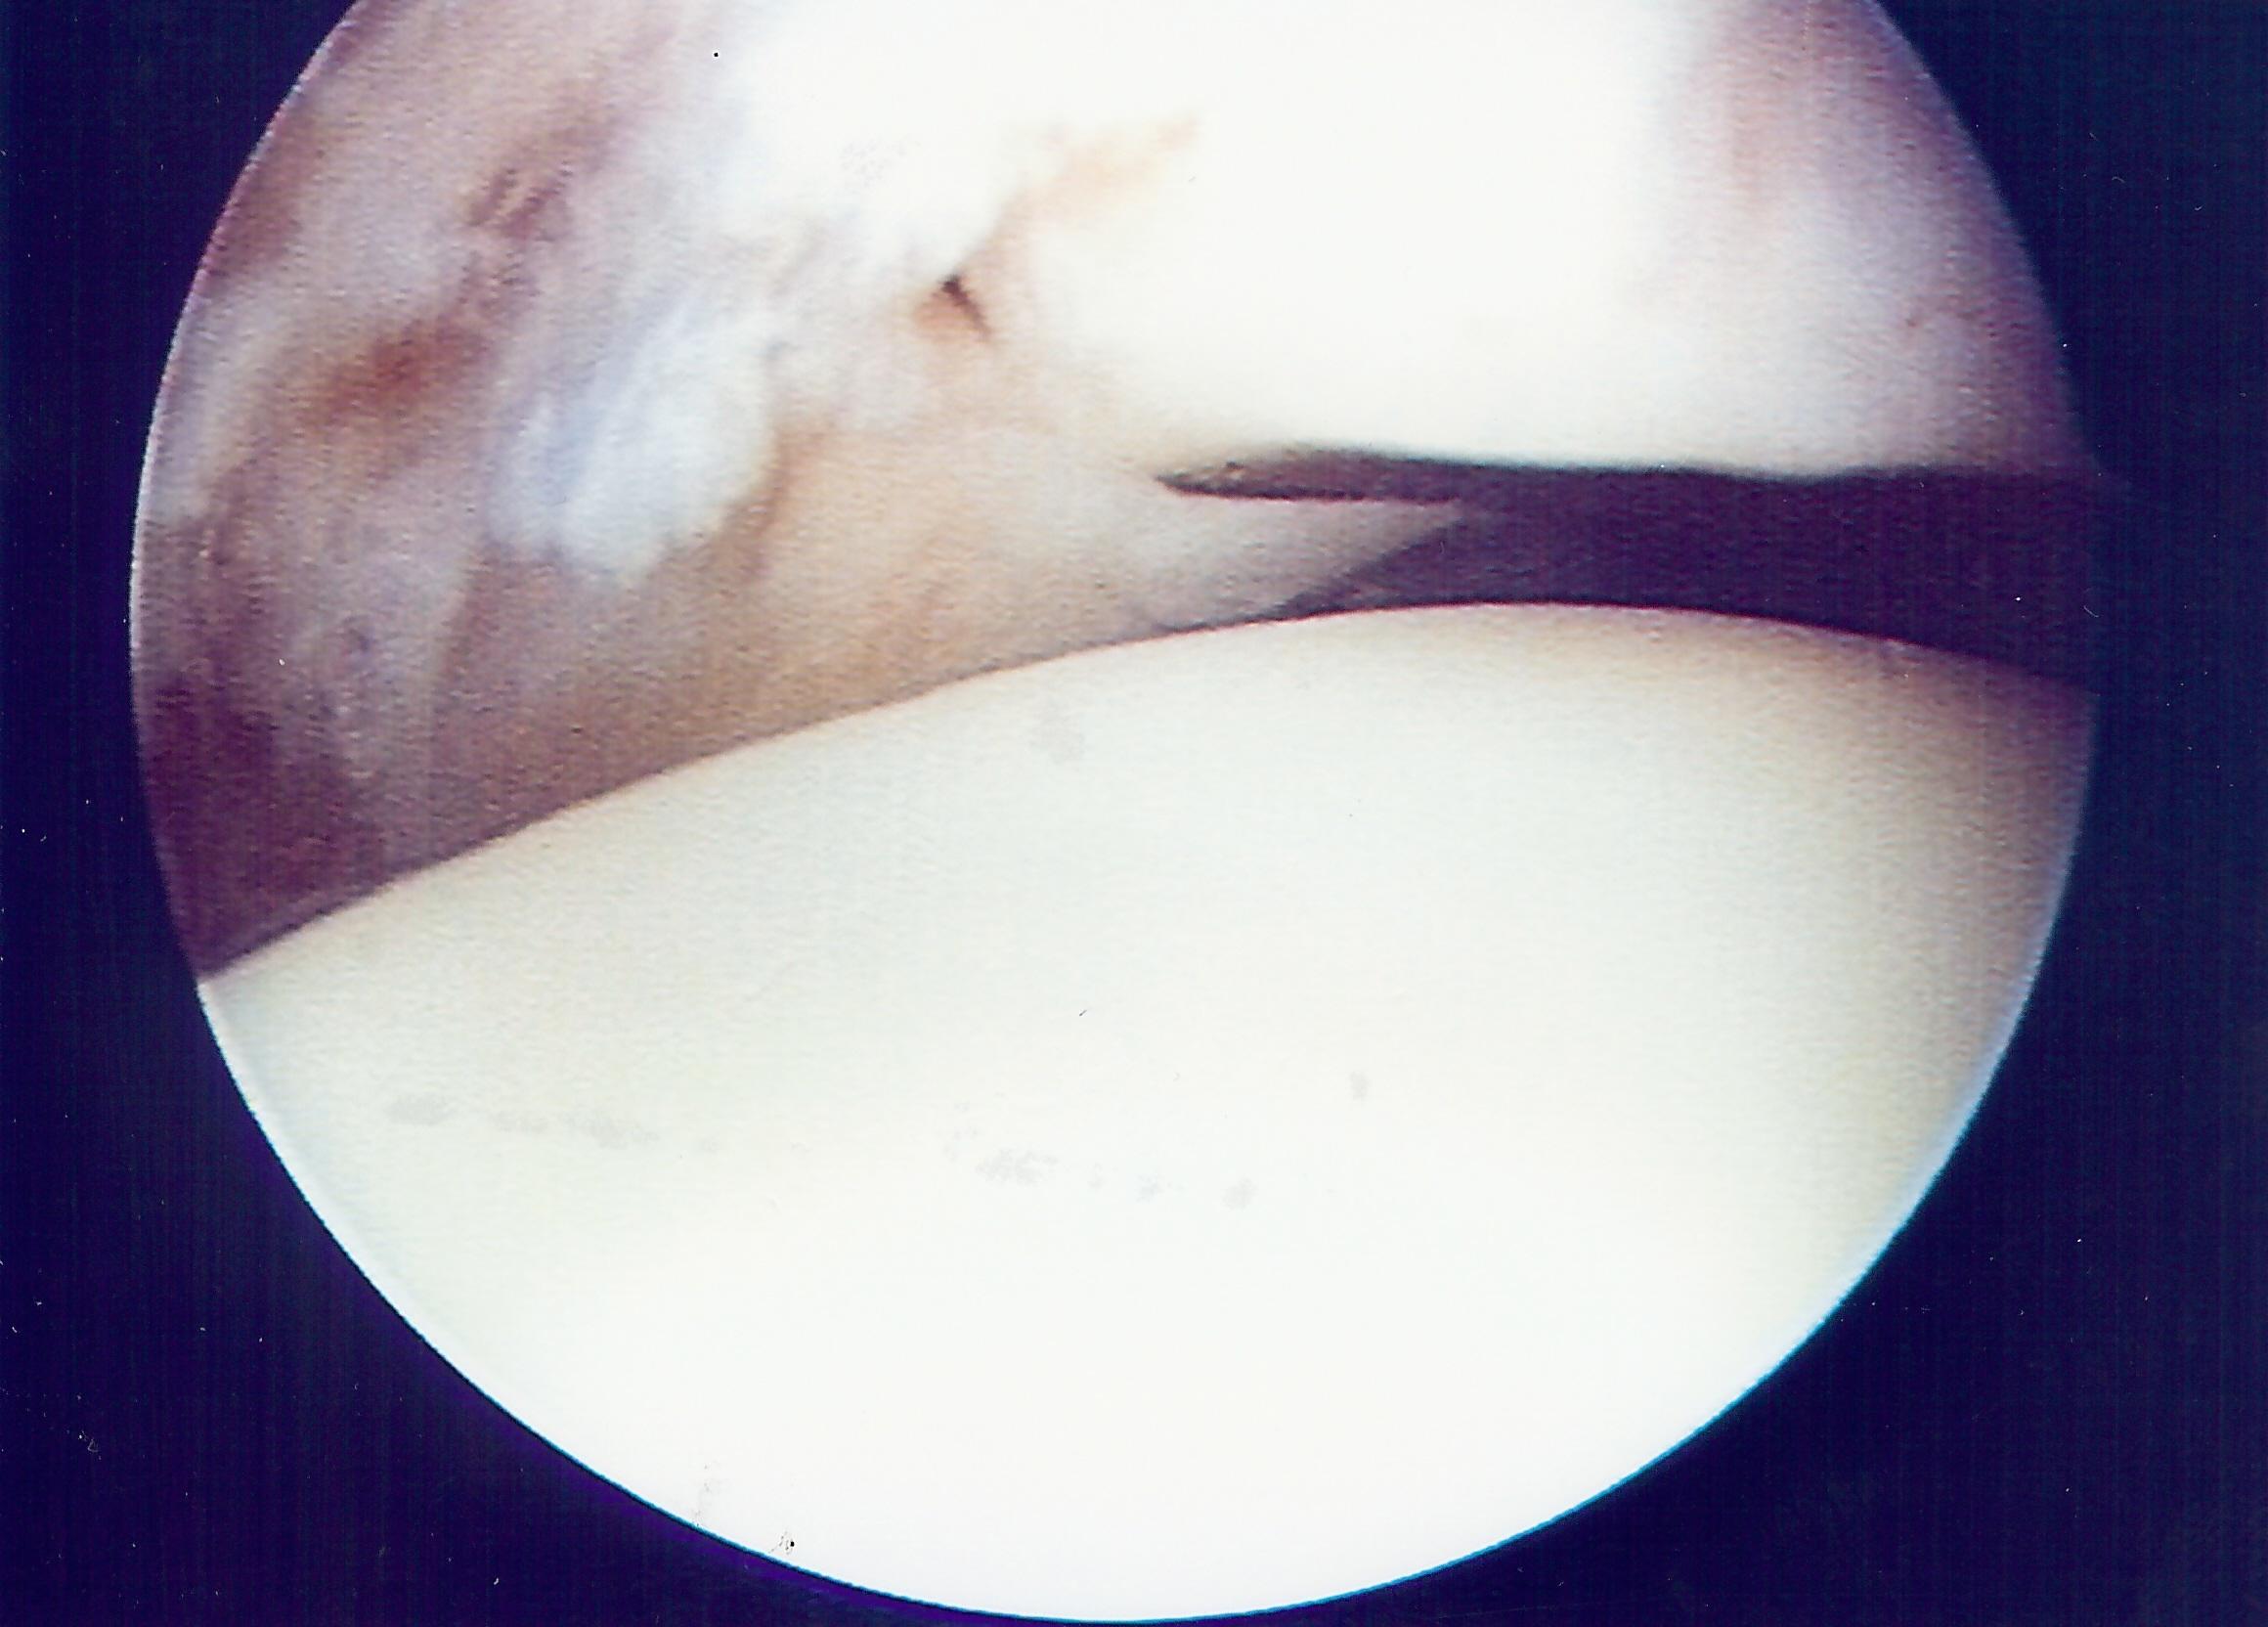

Ankle arthroscopy showing a “meniscoid lesion”. This is a fibrous “scar” that appears after an ankle injury that can get trapped in the joint, causing pain. Arthroscopic removal results in excellent pain relief.